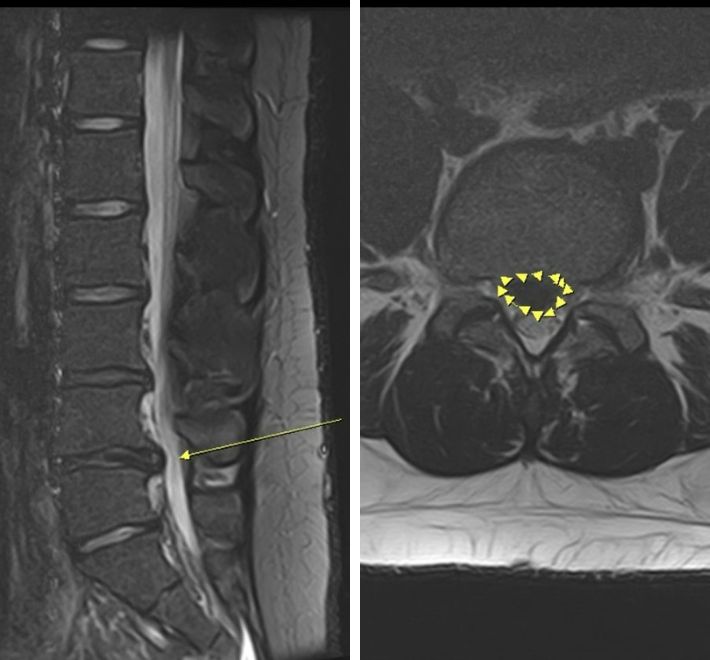

核磁共振 (MRI):這是診斷的黃金標準。能清晰顯示椎間盤突出的程度、水分含量以及神經受壓的神經根層次 。[3][4]

椎間盤突出的病理分類:膨出、突出、脫出與游離

臨床上,我們根據組織移位的程度將其分為四個階段,這影響了治療方案的選擇:

脫出 (Extrusion):髓核已穿破纖維環,在硬膜外腔形成腫塊。

游離 (Sequestration):髓核碎片掉入脊椎管內,與原椎間盤分離,最易導致嚴重神經壓迫。